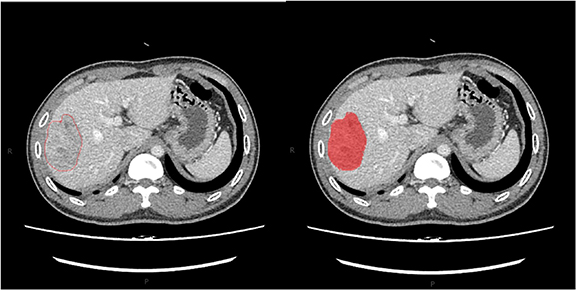

MaZda 4.6 software was used to calculate the texture features (Szczypinski et al 2009) (URL: www.eletel.p.lodz.pl/programy/mazda/). This software was developed within the European Cooperation In The Field Of Scientific And Technical Research project B11andhas been used in several research areas for all texture calculations (Jiang et al 2019). Lesions were evaluated on 1 mm thick images using the irregular shape of the region of interest (ROI). The size range of tumor ROIs was 11 mm2–68 mm2.Consistent quantitative measurements were performed by two abdominal radiologists with 12 and 8 years of experience. The primary radiologist selected the largest section of the lesion, manually drawing the ROI diagram (figure 1), and then the experienced senior radiologist confirmed the ROI setting, taking the lead when the two radiologists disagreed. We minimized the effects of contrast and brightness changes; otherwise, the true texture of the image would be blurred. To reduce the impact of contrast and brightness changes, we normalized the image gray intensity to m−3d and m + 3d (m, mean gray value; d, mean standard deviation) (He et al 2019).

Figure 1. The region of interest (ROI) of the tumor was drawn in red on MaZda (a free software for texture analysis).

Download figure: